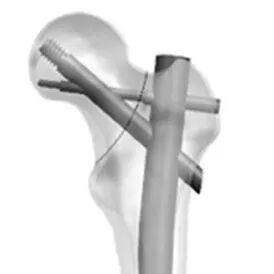

近年来,来自北医三院周方教授团队提出的PFUN,即proximal femoral universal nail system,股骨近端通用髓内钉系统,旨在通过增加内外侧壁的额外固定,即增加小转子螺钉,大转子冠状面螺钉或外侧钢板等,同时重建内外侧壁稳定性:

▲ 图A所示为PFUN系统中,小转子螺钉(c)与外侧壁螺钉(b),图B所示冠状面螺钉(c)。

▲ 图C所示为小转子螺钉(c)与外侧壁钢板(d);图D所示为PFUN三维力图模型。